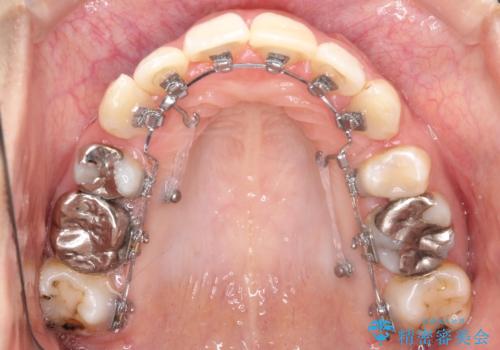

- 口元が出ていることを気にされて来院されました。精密な検査の結果、歯列全体のスペースが不足していることが判明。患者様のご希望である「口元を下げたい」というご要望を叶えるため、上下左右の小臼歯を抜歯し、そのスペースを利用して前歯を奥へ移動させる治療計画を立案しました。また、仕事上、目立つ矯正装置を避けたいというご希望から、上顎に裏側矯正、下顎に表側矯正を組み合わせたハーフリンガル矯正を提案しました。

今回の矯正治療では、口元を大きく下げるため、上下左右の小臼歯を抜歯しました。装置には、上顎は歯の裏側に装着する裏側矯正(舌側矯正)を、下顎は透明で目立ちにくい審美ブラケットを使用するハーフリンガル矯正を選択。これにより、治療中も他人の目を気にすることなく、ストレスなく過ごしていただけました。抜歯によってできたスペースを有効活用し、歯列全体を後方へ移動させることで、口元の突出感を解消。治療の結果、口元がすっきりと整い、自信のある美しい横顔を獲得していただけました。